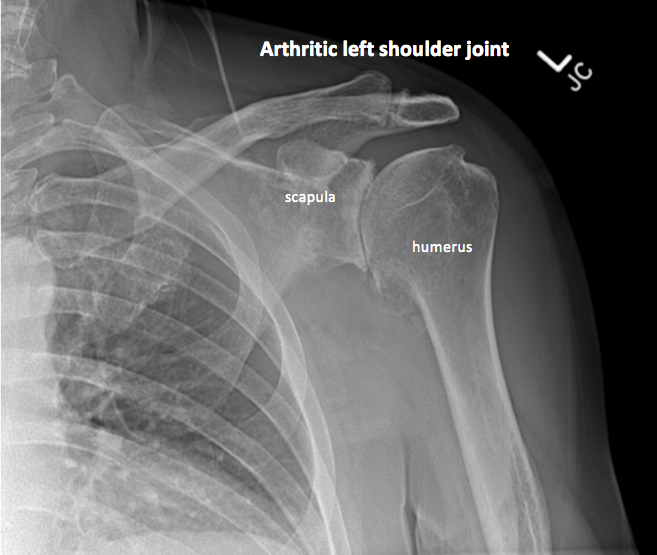

Shoulder arthritis — Dr. Nate Formaini

Shoulder Arthritis / Rotator Cuff Tears: causes of shoulder pain: B2 …

Shoulder Arthritis Austin, TX | Shoulder Surgery Austin, TX …

Shoulder Arthritis / Rotator Cuff Tears: causes of shoulder pain …

Shoulder Arthritis (Glenohumeral Arthritis) — Andrew Dold, MD …

shoulder xray oa3 – DOCJOINTS//DR SUJIT JOS//Total joint replacements …

Shoulder Arthritis Austin, TX | Shoulder Surgery Austin, TX …

Arthritis — Dr. R. Edward Glenn, Jr.

Arthritic shoulder, X-ray – Stock Image – M110/0586 – Science Photo Library

Shoulder Arthritis / Rotator Cuff Tears: causes of shoulder pain …

Shoulder Arthritis / Rotator Cuff Tears: causes of shoulder pain …

Shoulder Arthritis / Rotator Cuff Tears: causes of shoulder pain …

Shoulder Osteoarthritis Presentation and Treatment | Bone and Spine

Shoulder Arthritis / Rotator Cuff Tears: causes of shoulder pain …

Arthritic shoulder, X-ray – Stock Image – C007/1923 – Science Photo Library